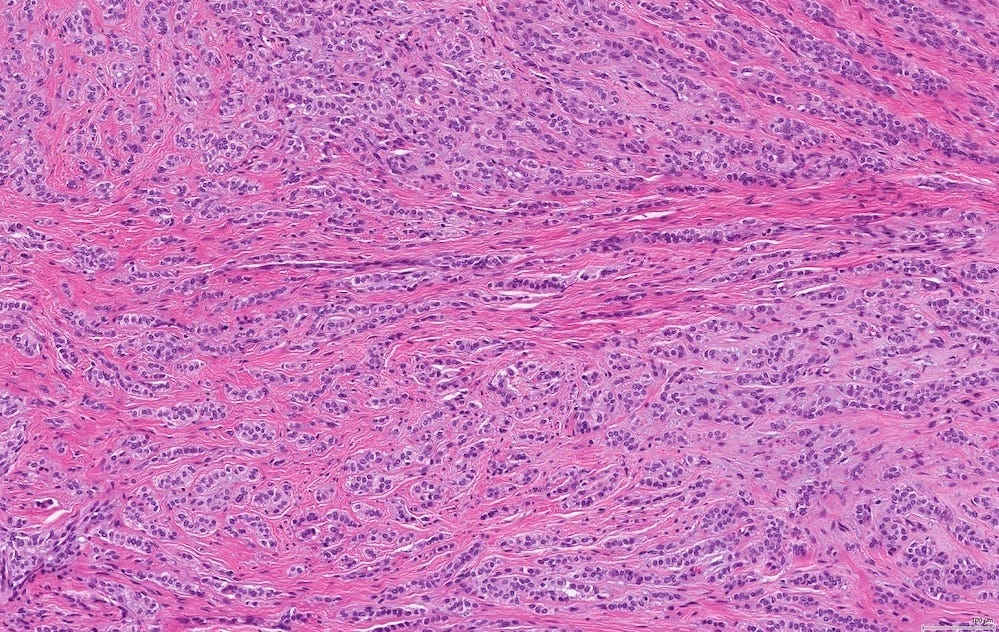

Microscopically, medullary carcinoma is composed of large, pleomorphic, high grade tumor cells arranged in broad syncytial sheets occupying at least 75% of the tumor area. The tumor cells have vesicular nuclei (i.e., large, pale staining with a central clearing) with prominent nucleoli and abundant eosinophilic cytoplasm. A prominent and dense lymphoplasmacytic infiltrate surrounds and often infiltrates the tumor, suggesting a vigorous host immune response. Mitotic figures are numerous and areas of necrosis may be present.

Medullary carcinoma - radiologic and microscopic images